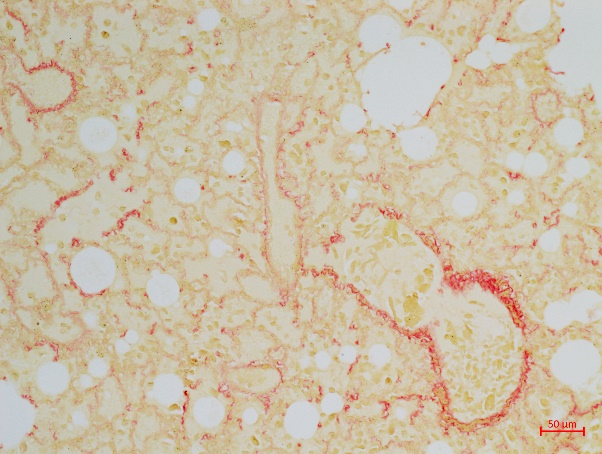

3、油红O染色实验结果(大鼠肝脏举例)

油红O染色实验结果解读:组织内着色为红色或者橘红色的部位为脂肪分布位置。